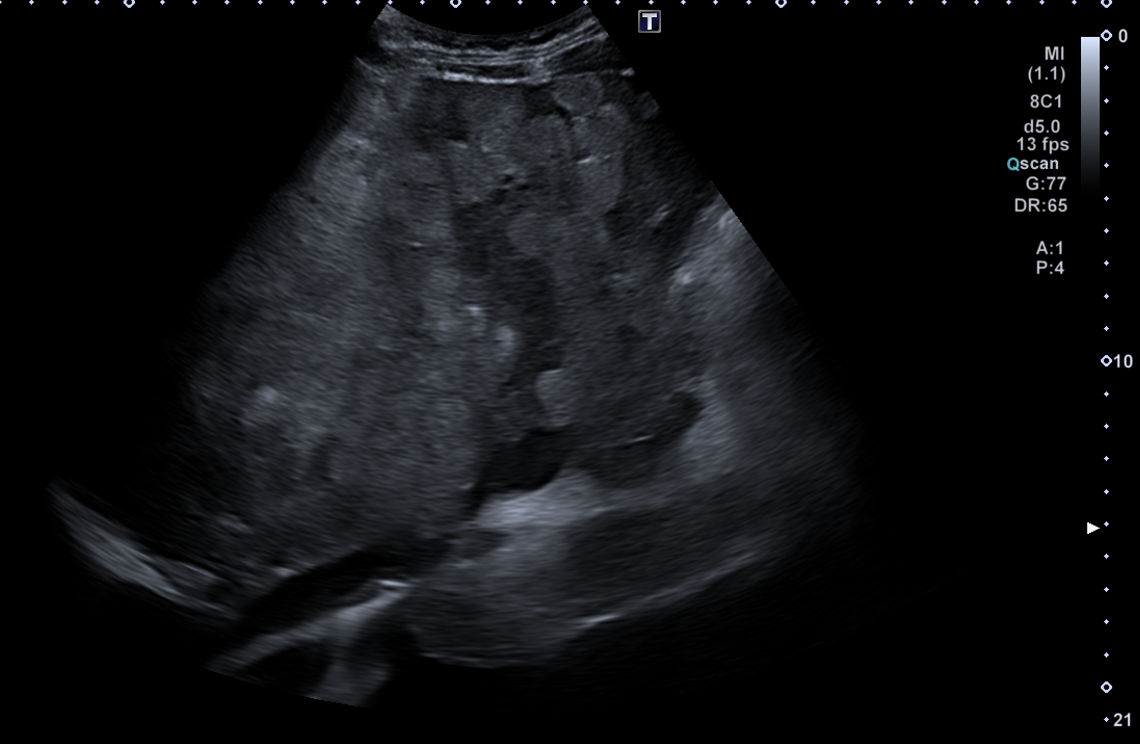

En ecografía en Centro de Salud: La práctica totalidad del parénquima hepático se encuentra sustituida por múltiples lesiones sólidas nodulares hiperecoicas, de predominio en el lóbulo hepático derecho, donde presentan tendencia a la confluencia y conforman una masa que alcanza los 13 cm de diámetro máximo. La vena porta es permeable y ectásica, con esplenomegalia. Ambos son signos de hipertensión portal.